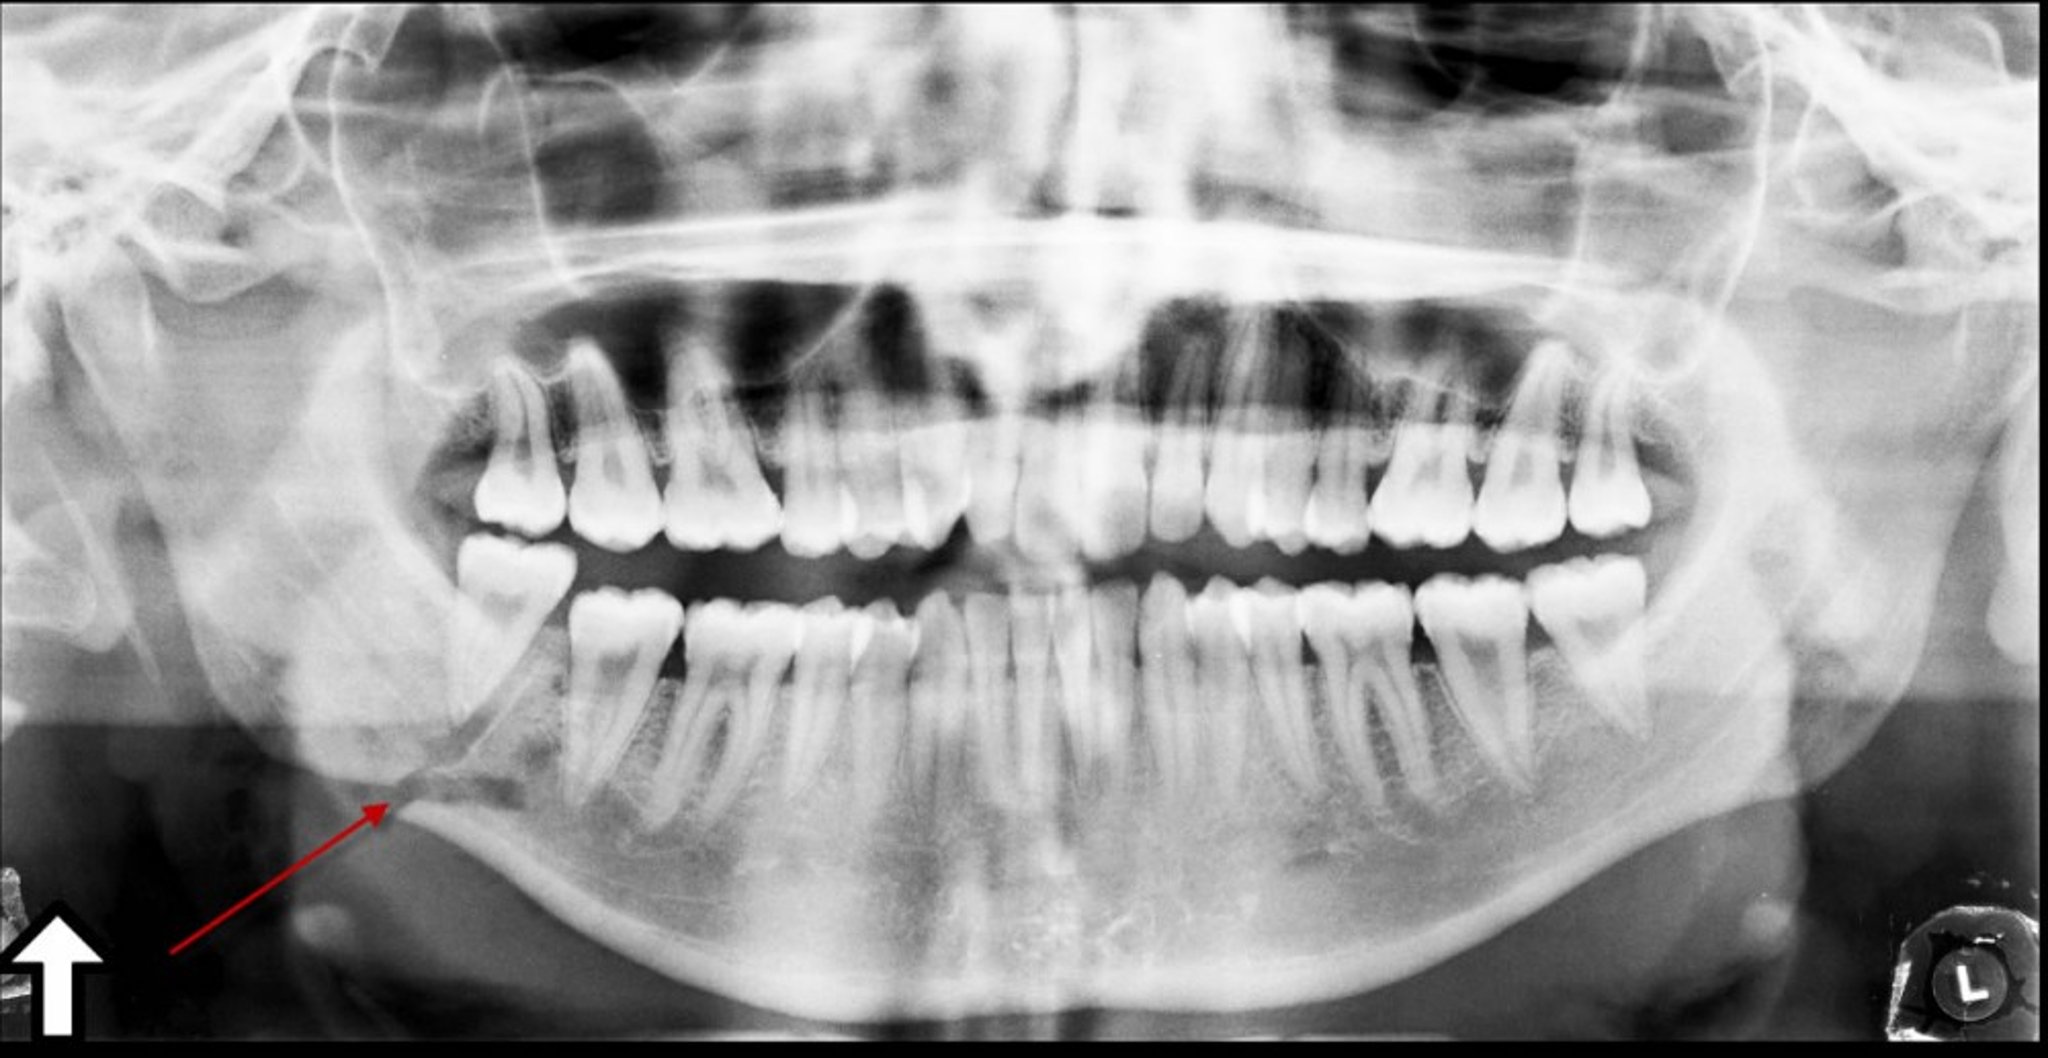

Fracture of the Angle of the Mandible

This panoramic radiograph shows a lucency (arrow) at the angle of the mandible, representing a fracture.